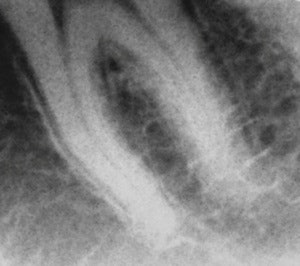

Real Time Imaging Technologies has developed a prototype that provides low-dose dental imaging and dental fluoroscopy imaging at comparable resolution to existing dental technologies. Images courtesy of Real Time Imaging Technologies."Despite its early introduction to dentistry in 1896, the use of fluoroscopy in this profession has been inconsistent over the last 55 years due to radiation dosage concerns and the large size and low resolution of the devices used," he and his colleagues wrote in 2010 (Chinese Journal of Dental Research, Spring 2010, Vol. 13:1, pp. 23-29).

Raw image obtained from a dental fluoroscopic imaging system intraoral/extraoral sensor working prototype on a dental phantom at 0.2 mA/0.033-second exposure time.